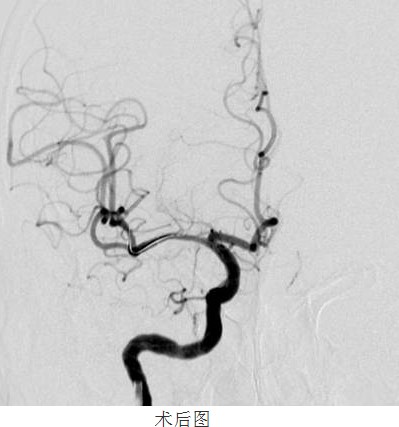

常规准备后,神经内科颜津津主治医师在助手高彬医师配合下采用Seldinger法穿刺股动脉,置导管鞘、引导管,在导丝带引下将导引导管放置右侧颈内动脉岩部造影,后在透视下,顺着造影路图,小心将微导丝、微导管通过狭窄处并置入右侧大脑中动脉M3段,接着撤出微导管,顺着微导丝置入Gateway球囊, 至狭窄部位,经造影骨性标志等多重定位后证实球囊位置良好,接压力泵缓慢加压扩张,撤出球囊造影,显示血管成形良好。选取Wingspan支架, 顺微导丝将支架输送器小心送至狭窄处,造影定位确认支架位置准确覆盖狭窄部位,释放支架,撤出支架输送器,造影证实血管狭窄处成形良好,观察10分钟后再次造影,支架无移位,狭窄处远端血管完整,未见血管狭窄、造影剂外渗。撤除导丝、导引导管,患者术后24小时可下床自行活动,术后1周顺利出院,生活基本恢复正常,并叮嘱梁伯继续坚持服药,定期复诊。

“大脑中动脉血管成形及支架植入术”为我院首例颅内支架植入手术,其顺利完成,标志着我院在神经介入诊疗方面的水平又上了一个新的台阶!